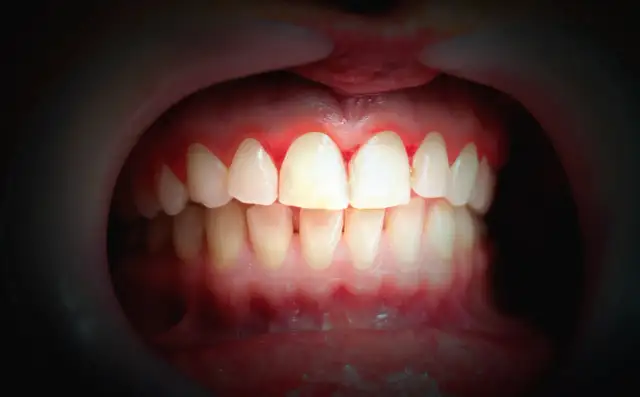

Aby lepiej zobrazować różnicę, przygotowałam porównanie wyglądu zdrowych dziąseł i tych dotkniętych zapaleniem:

| Zdrowe dziąsła | Dziąsła w stanie zapalnym |

|---|---|

| Mają naturalny, bladoróżowy kolor. | Są intensywnie czerwone lub sino-czerwone. |

| Są zwarte i jędrne w dotyku. | Są nabrzmiałe, spuchnięte i często wydają się "rozpulchnione". |

| Nie powodują dyskomfortu ani bólu. | Mogą być bolesne i tkliwe na dotyk. |

Oprócz widocznych zmian, zapalenie dziąseł często manifestuje się poprzez uczucie bólu, tkliwości i ogólnego dyskomfortu. Może to utrudniać codzienne czynności, takie jak jedzenie czy właśnie mycie zębów. Dziąsła stają się wtedy bardzo wrażliwe, a każdy dotyk może wywoływać nieprzyjemne odczucia.